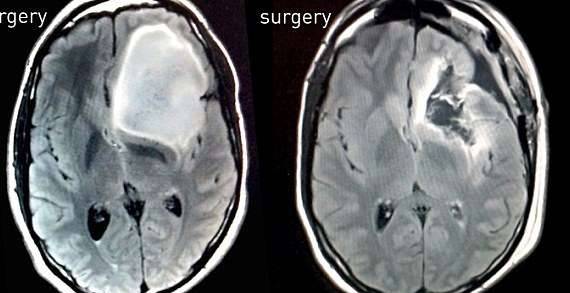

▼医生发现基廷脑部的肿瘤阴影。

然而七年之后,也就是2014年,肿瘤竟然发展到了棒球大小,甚至影响了他的嗅觉。

▼肿瘤足足有棒球大小,位于左侧大脑,紧靠嗅觉神经区域

情况糟糕到不得不进行手术,在为期三个月的準备之后基廷开始了这场历时10个小时的手术,这个科学怪人要求手术过程全程录像,幸运的是手术很成功,之后的化疗用了一年的时间。